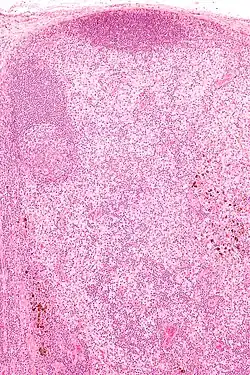

Micrograph showing dermatopathic lymphadenopathy with the characteristic paracortical histiocytosis and melanin-laden macrophages. H&E stain.

• Paracortical histiocytosis

• Melanin-laden macrophages

• Eosinophils

• Plasma cells (medulla of lymph node)